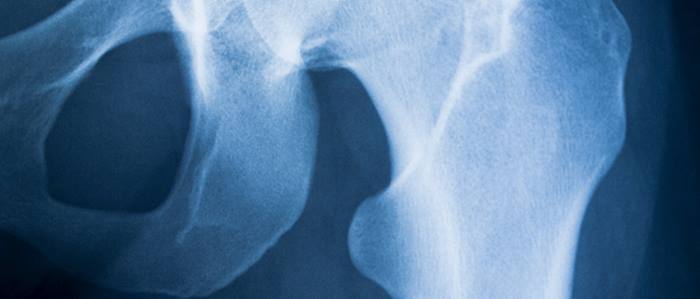

Knee Injuries

Knee injuries often involve tears or ruptures to one of four major ligaments that connect the bones in the knee joint. The most common is the ACL, or anterior cruciate ligament .